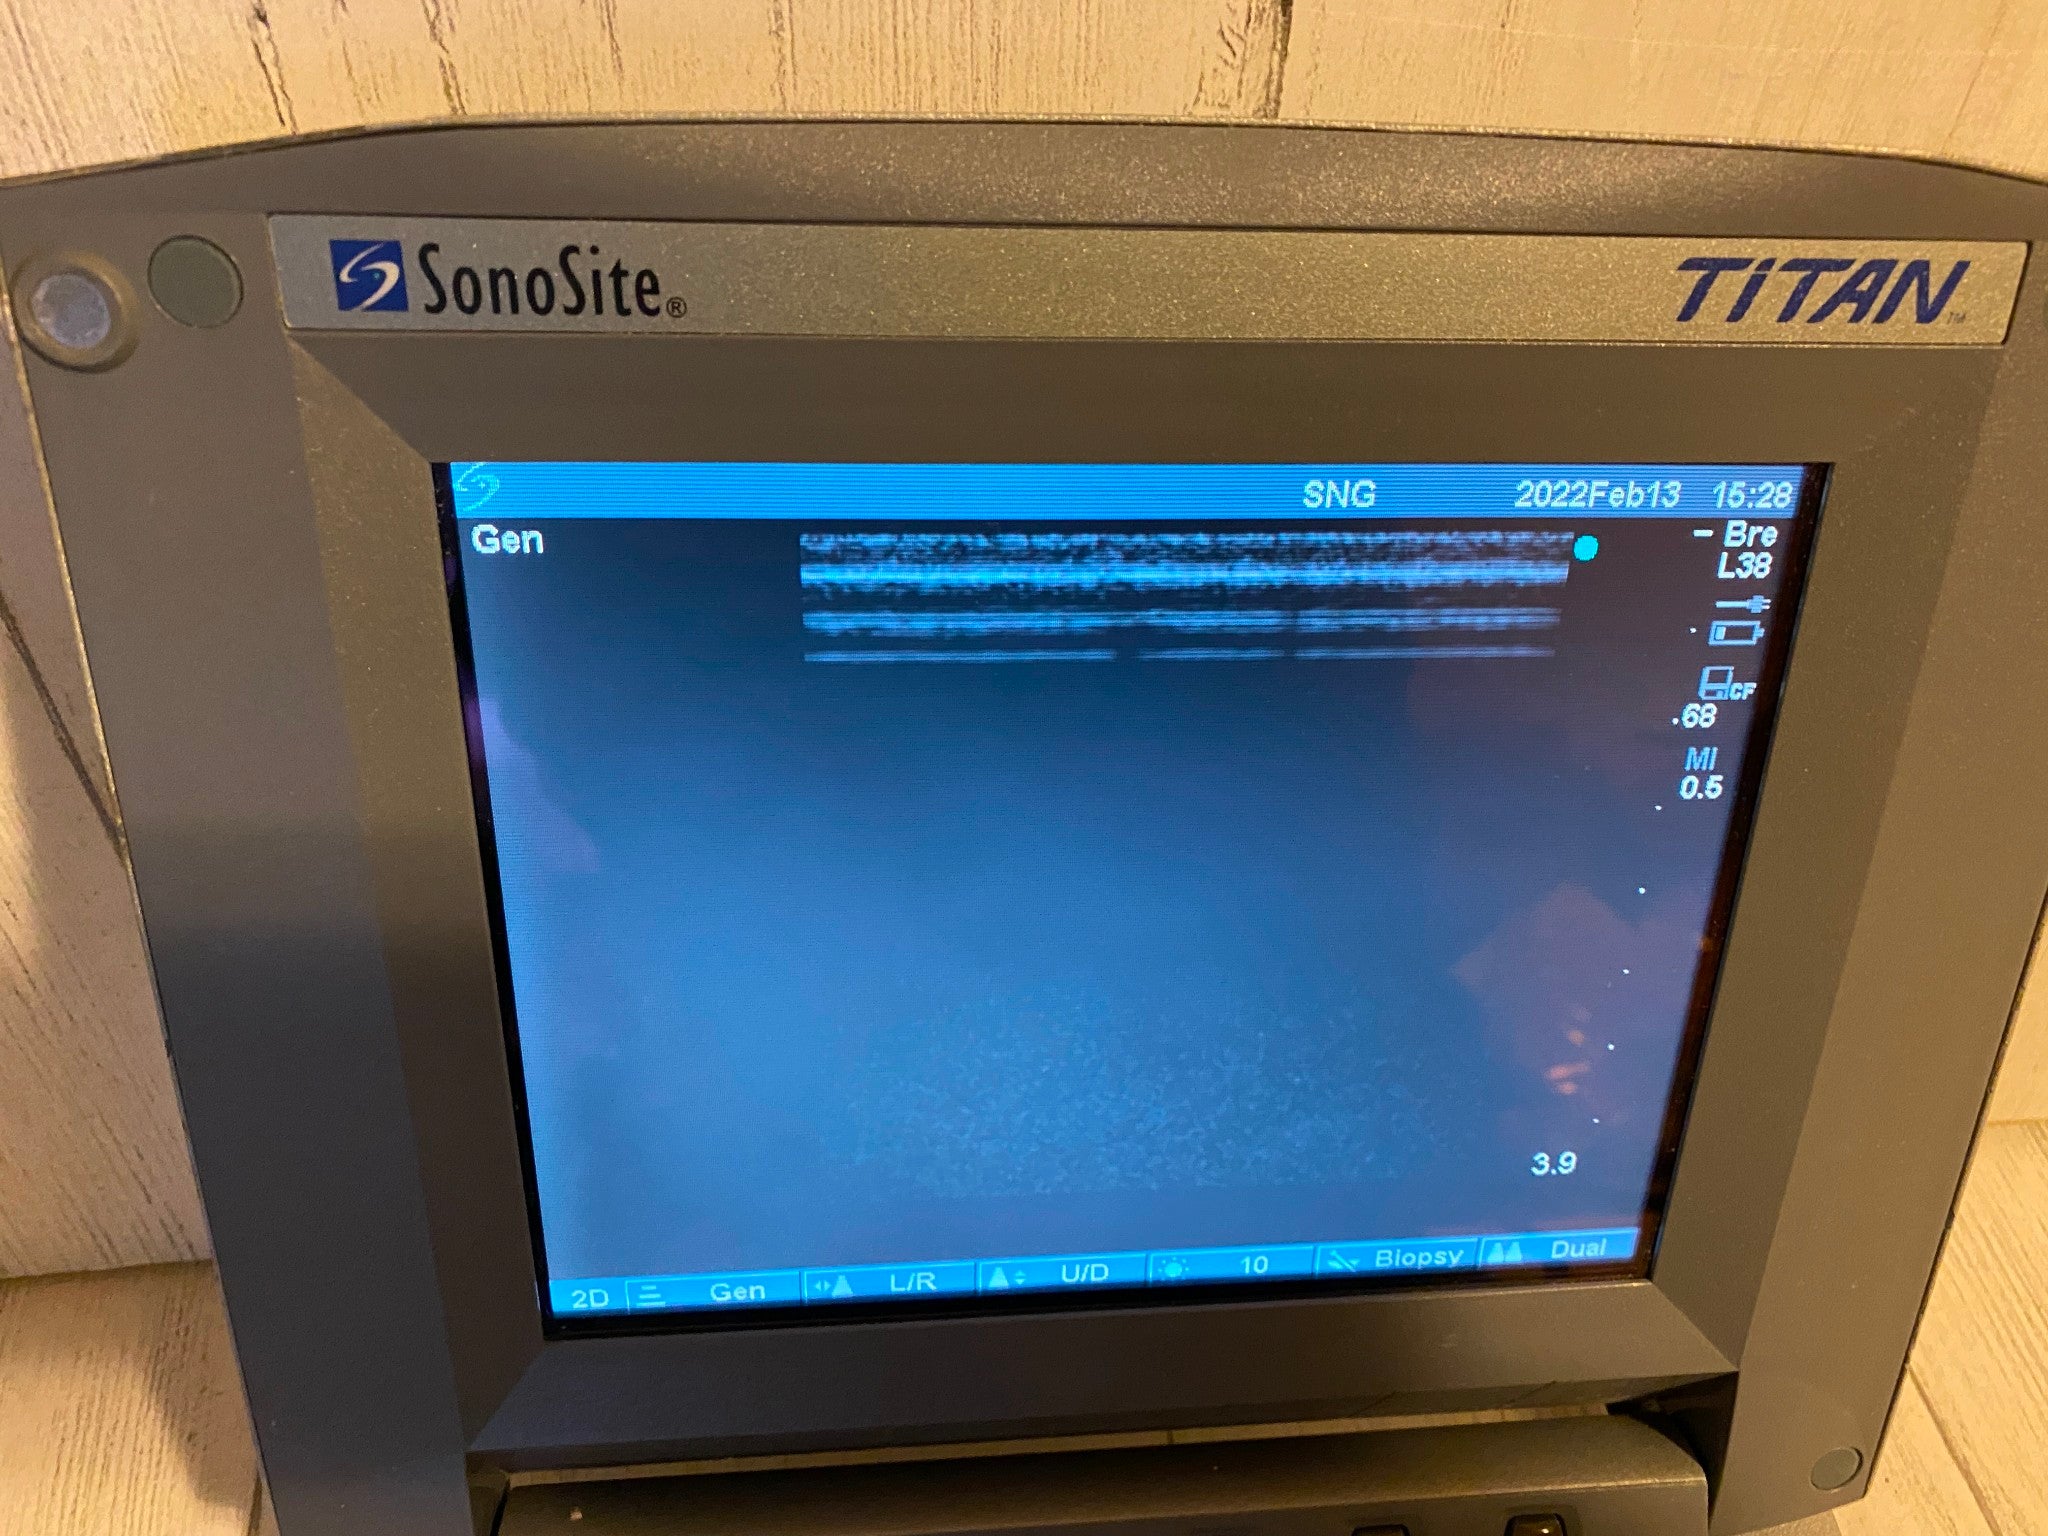

Linear Array L38/10-5Mhz For Sonosite Titan Portable Ultrasound 2013

Sale price$ 1,199.20

Regular price$ 1,499.00